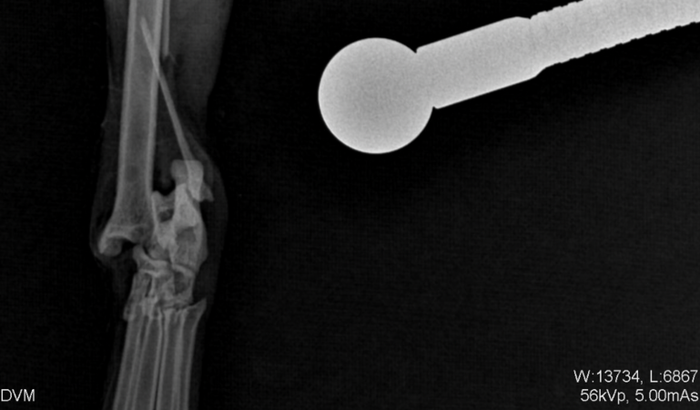

A nossa gatinha foi atacada por um cachorro, e teve uma fratura completa e precisará de uma cirurgia, a cirurgia ficará em torno de 2.390,00 fora os medicamentos, porem nao temos condições de arcar com todos os gastos, sua ajuda será muito importante… Qualquer quantia ajuda